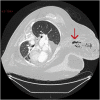

Case presentation: We describe a 54-year-old lady who presented with breast erythema and raised inflammatory markers. Initially treated as cellulitis, however when her symptoms did not improve and despite IV antibiotics her bloods worsened, a CT scan was performed which showed a large volume of interstitial soft tissue gas with diffuse fat stranding, consistent with necrotising fasciitis. Debridement of her breast alongside the use of sensitive antibiotics and ITU support led to a satisfactory outcome.

Discussion: We discuss how an early diagnosis can be made by the recognition of a triad of symptoms common in necrotising fasciitis, and how optimal management can be achieved with the incorporation of imaging to successfully identify the condition and allow targeted debridement of the areas of necrotising fasciitis.